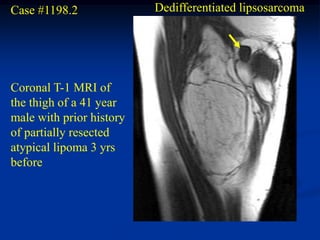

Case #1198.2              Dedifferentiated lipsosarcoma

Coronal T-1 MRI of

the thigh of a 41 year

male with prior history

of partially resected

atypical lipoma 3 yrs

before

Case #1198.2 Dedifferentiated lipsosarcoma Coronal T-1 MRI of the thigh of a 41 year male with prior history of partially resected atypical lipoma 3 yrs before